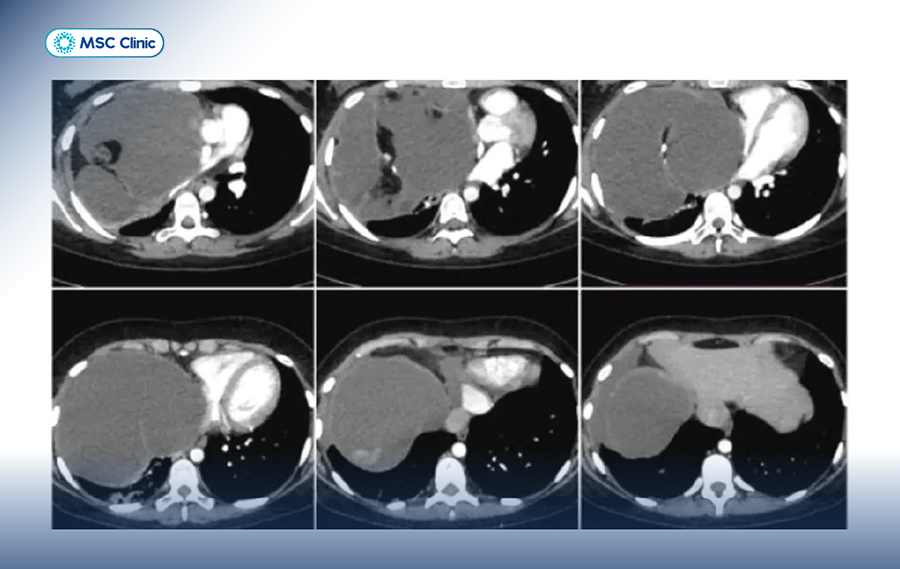

Chẩn đoán hình ảnh nâng cao và xâm lấn:

Gan trên hình chụp CT